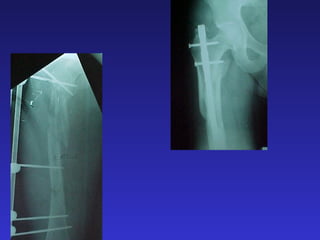

FRACTURAS DIAFISARIAS DE

FEMUR

UNIVERSAL

CRM MASC. 35 Años PO